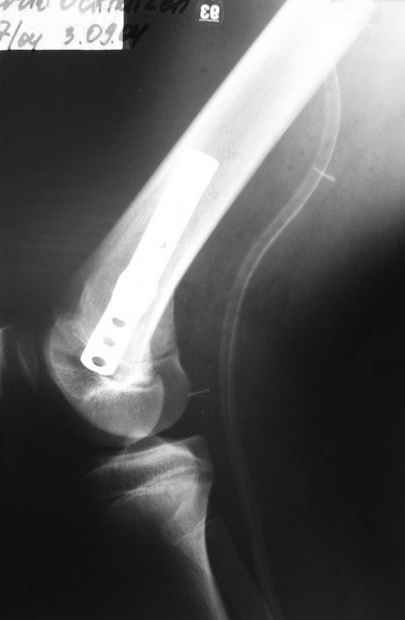

Уважаемые коллеги!На прием обратилась больная 38 лет. Травма 17.01.2005. 23.01.2005 - операция в одном из стационаров области - остеосинтез мыщелка бедра винтами, Остосинтез мыщелка большеберцовой кости L-образной пластиной.

Август 2005

Остальные снимки Ноябрь 2005

Иммобилизация лонгетной гипсовой повязкой 2 мес. После прекращения иммобилизации, пр начале ЛФК отмечена нарастающая вальгусная деформация конечности. Рентгенограммы в приложении. Хотелось бы узнать Ваши предложения по тактике лечения